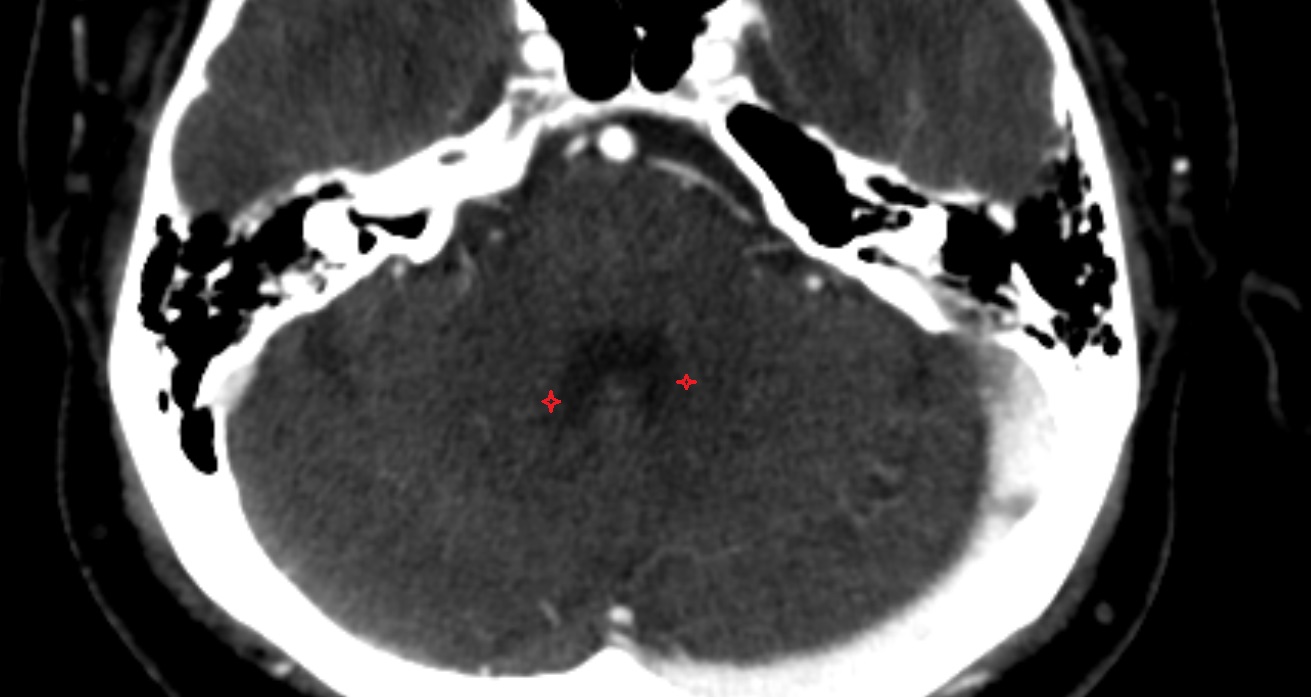

- Cerebellum

- Cisterna magna

- Premedullary cistern